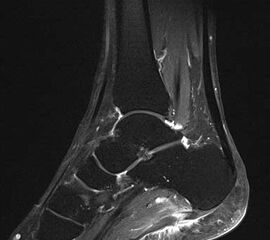

Hier befindet sich ca. 3-5 cm proximal des Tuber calcanei ein als „kritische Zone“ benannter Bezirk, der durch eine ungünstige arterielle Blutzufuhr gekennzeichnet ist (letzte Wiese). Hier finden sich häufig spindelförmige Schwellungen, die bei MRT-Diagnostik nicht selten partielle Nekrosen und Partialrupturen der Achillessehne aufweisen (Abb. 14).

Unabhängig davon können insbesondere chronische Insertionstendinosen der Achillessehne von Partialrupturen (Abb. 15) und erosiven Läsionen des dorsalen Fersenbeines begleitet sein.

Bildgebung

Die sonographische Diagnostik eignet sich primär zur Erkennung schmerzhafter Prozesse im Verlauf der Achillessehne und kann bei Bedarf durch Röntgen bzw. MRT ergänzt werden. Besonders bei längeren Verläufen und kräftigen spindelförmigen Schwellungen (>9mm, Normwert <5mm) im Bereich der kritischen Zone sollte ein MRT zum Ausschluss von Nekrosezonen und Partialrupturen vor Therapiebeginn veranlasst werden. Die sonographisch leicht zu erfassende Veränderung der Sehnendicke im mittleren Sehnenanteil ist ein guter Indikator für die Schwere der Erkrankung und die Beurteilung des Behandlungsverlaufes. Die sichtbaren Veränderungen am distalen knöchernen Ansatz der Sehne sind diskreter.

Insbesondere bei größeren Partialrupturen (Abb. 14) sollten operative Verfahren erörtert werden. Kleinere Partialrupturen sind der ESWT gut zugänglich, wie die beiden nachfolgenden Beispiele zeigen: